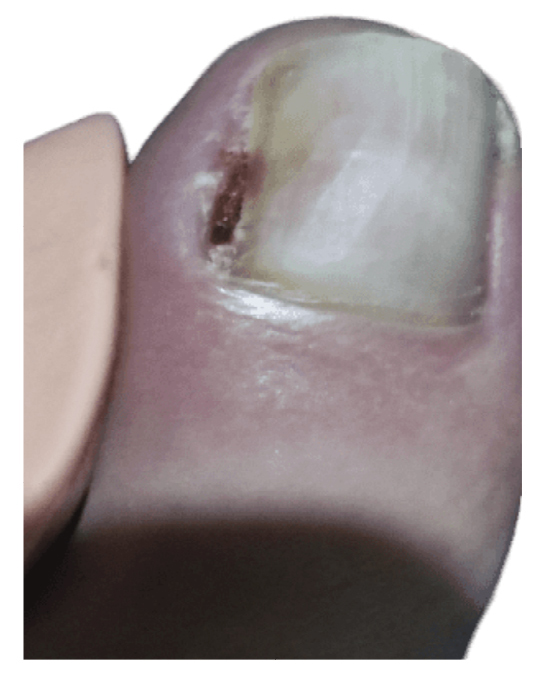

The patient reported a 7-month history onychocryptosis (September 2022) on the medial border of the first toe of the left foot, with presence of ungual granulation tissue on said border, causing her pain and digital inflammation (Figure 1). The patient received treatment from her podiatrist consisting of chiropody and canal cleaning, and then daily dressings with mupirocin were prescribed for the lesion. The lesion showed poor progression in the following days with increased pain and tenderness to the touch. Treatment was modified to amoxicilin/clavulanic acid 875/125 mg, 1/8 hours along with the use of oral analgesics (Figure 2). The patient continued with poor symptomatic evolution and attended her health center where an X-ray was performed, ruling out the presence of deep infection (osteomyelitis).

Figure 1. Initial process of onicochryptosis and reactive granuloma.